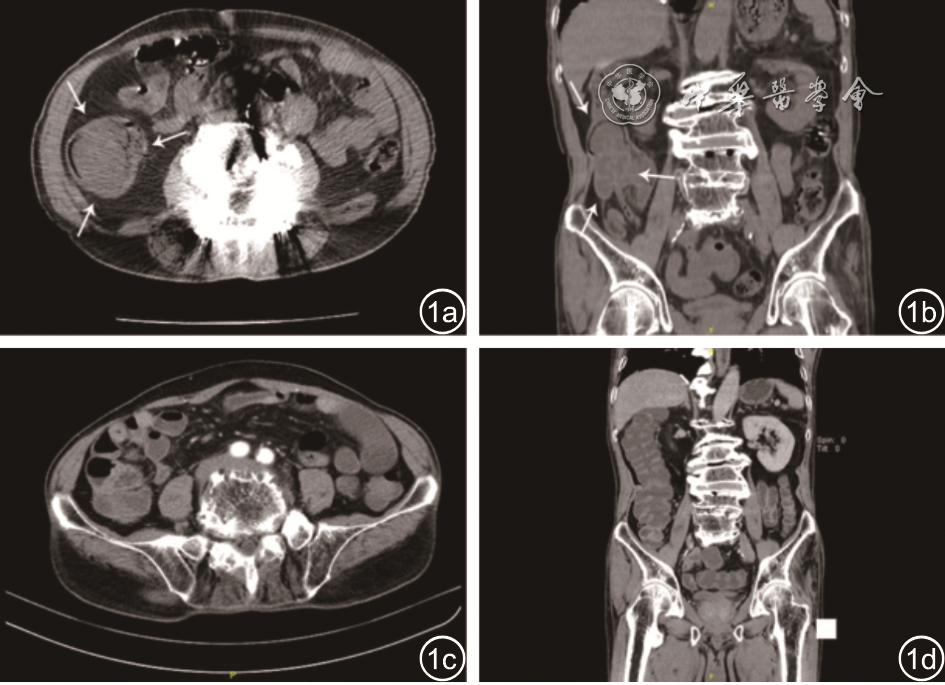

图2 患者肠镜与病理(HE×10)检查。图a、b:可见盲肠隆起,覆黄色分泌物,无法冲掉,盲肠底部见不规则型浅溃疡及糜烂;图c:炎性渗出及坏死组织,其间可见较多杆菌,另见少量间质;图d:治疗后复查可见盲肠瘢痕